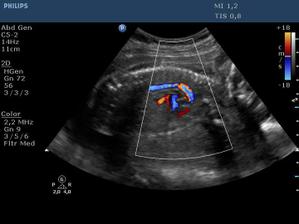

Ultrazvuk miminka - 24 týden

Z "menší protekce" u pana primáře Radiodiagnostického oddělení jsme mohli na soukromou "špionáž" naší krásné holčičky... (Pan doktor je už třetí, kdo hádá holčičku a po pravdě s tím přístrojem, co má k dispozici, bylo naprosto zřetelně vidět, že tam žádný pytlík není! :o)) Natočil nám i několik videí, kde ta naše šibalka zívala a dvakrát na nás dokonce vyplazovala jazyk. ;o)